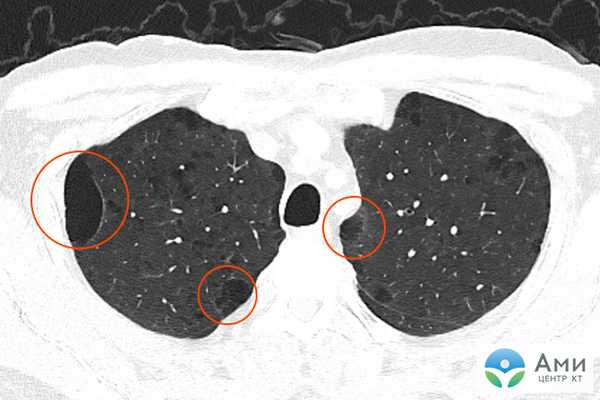

Оценивая данные КТ легких, врач-рентгенолог дифференцирует заболевания по специфической картине «матовых стекол»: их количеству, локализации, наличию других признаков, по которым возможно определить причину патологических изменений ткани легких. Например, для двусторонней вирусной пневмонии характерно наличие «матовых стекол», расположенных периферически в нижних и задних отделах легких. В более поздней стадии наблюдается консолидация очагов инфильтрации с утолщением перегородок альвеол.

«Матовые стекла» при туберкулезе могут быть расположены рядом с бронхами или диссеминированы — в этом случае наблюдается множество маленьких светлых участков (инфильтратов), хаотично расположенных во всей полости легких. Также при туберкулезе на КТ легких можно обнаружить характерные фиброзные тяжи, ведущие к корню легкого — это перибронхиальное воспаление, признаки лимфостаза с увеличением лимфатических узлов. Единичные участки «матового стекла» малого размера без четкого паттерна какого-либо заболевания могут указывать на новообразование, развивающийся фиброз, аденокарциному (рак) легких.

Общим признаком острых пневмоний на КТ является наличие инфильтратов («матовых стекол») разной формы и протяженности. «Матовые стекла» расположены вокруг очагов или диффузно, как при туберкулезе. Однако в отличие от туберкулеза, их размер обычно больше, есть тенденция к консолидации инфильтратов и образованию рисунка по типу «булыжной мостовой». В отдельных случаях визуализируются просветы бронхов, содержащих газ. Это называется синдромом «воздушной бронхографии». В сочетании с эффектом «матового стекла», он также относится к явным признакам пневмонии.